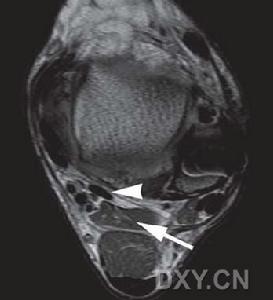

主治 出處 定位 取法 解剖關節屈曲過程中增加步態推離相,並吸收對跖骨頭的衝擊力。當長屈肌通過跖趾關節底短屈肌腱間時,籽骨對長屈肌腱起重要保護作用。籽骨系統將各種屈肌力在前...外側。踇外翻的矯形術中,由於收肌與短屈肌從腓側籽骨出來的肌纖維聯合附著於近...

籽骨的胚胎 籽骨的解剖與功能 籽骨的生物力學研究 籽骨與外翻的關係 兩分籽骨肌腱、趾長伸肌、踇長伸肌。皮膚由腓總神經的分支腓淺神經分布。腓骨長、短肌由腓淺神經的肌支支配,踇長屈肌和趾長屈肌由脛神經支配。(參看光明穴...。或定於腓骨後緣與腓骨長、短肌之間凹陷處。《針灸甲乙經》:“在足外踝上...